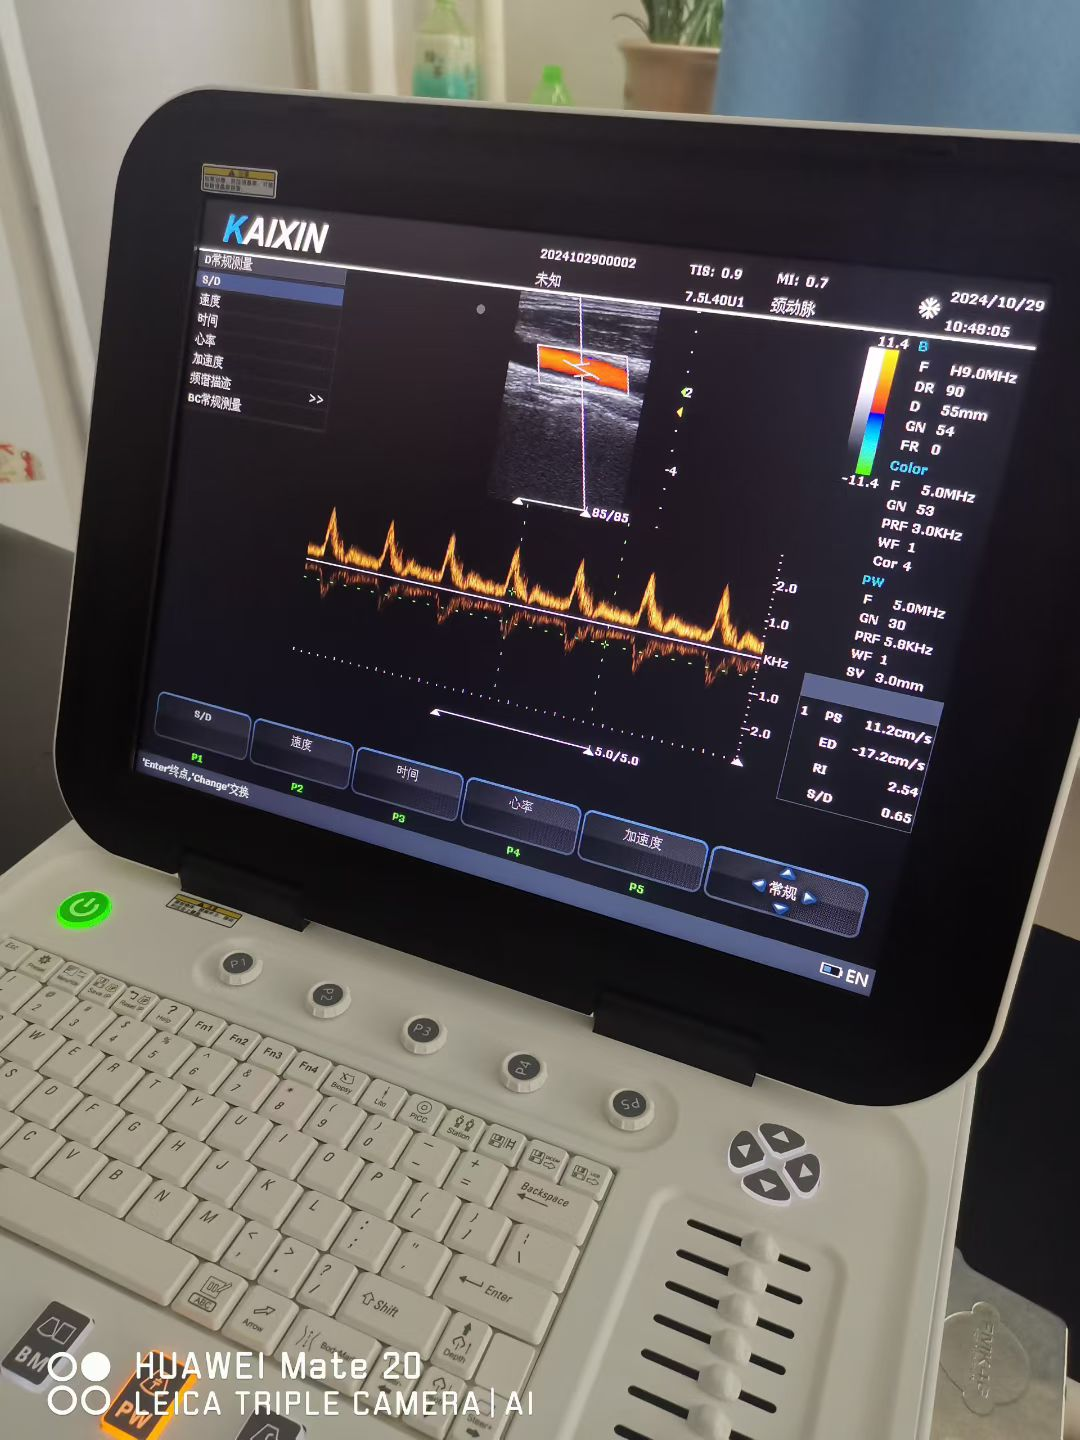

便携B超与碎石机配合,核心应用是在泌尿系统结石治疗中实现“实时定位-精准碎石-疗效确认”的闭环操作,尤其适用于门诊、急诊或床旁等移动医疗场景。1. 核心应用场景:泌尿系统···...

具体重要性体现在以下三点: 1、适配基层场景:体积小、重量轻,可在村委会、村卫生室等简易场所快速部署,无需专门的大型检查室,甚至能为行动不便的老人上门检查,极大提升了下乡···...